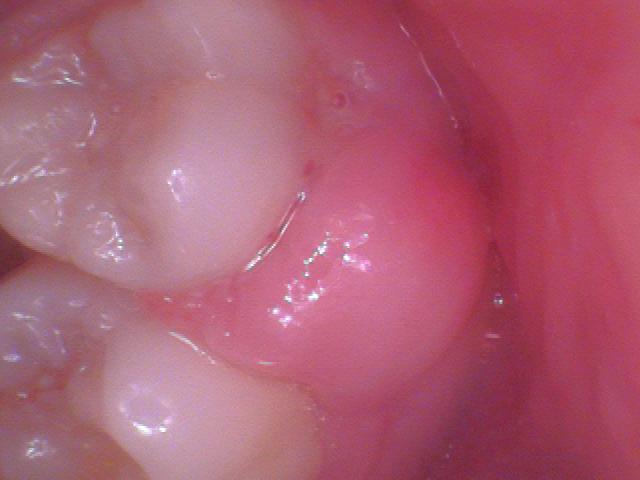

What is a Pregnancy Tumor?

Pregnancy tumor or pyogenic granuloma is a vascular lesion that occurs on both mucosa and skin, and appears as an overgrowth of tissue due to irritation, physical trauma or hormonal factors